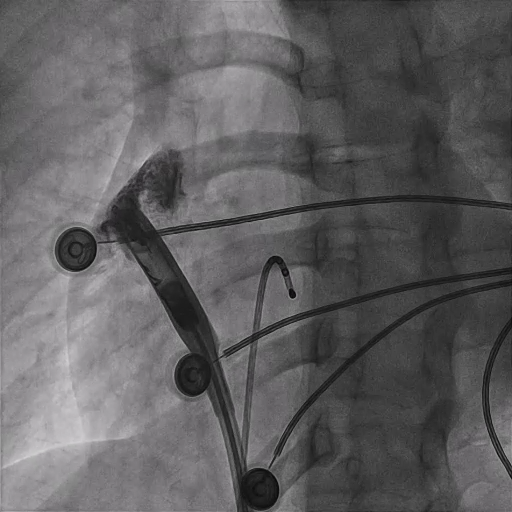

2026 年 1 月,北京协和医院程康安教授、陈太波教授为患者实施了 AVIER™ AR心房无导线起搏器植入手术。手术团队提前周密部署,术中先为患者放置临时起搏电极并进行心房起搏测试,确认可实现 120 次/分 心房起搏下,房室结1:1的传导,且右心耳基底部起搏阈值正常,完全满足植入条件后,才开始植入心房无导线起搏器。

手术采用右侧股静脉微创入路,将无导线起搏器送至右心耳基底部。植入过程中,以 “固定可靠 + 电学参数表现理想” 为双重目标,在定位与旋入阶段,持续监测阻抗及损伤电流等即时反馈,以此评估组织接触质量与主动固定效果。

整个植入过程十分高效顺利,耗时30分钟,术中测试下腔阻抗280Ω,从mapping至对接栓模式阻抗高低变化:310Ω-320Ω-330Ω-320Ω-310Ω,张力测试确认头端螺旋固定牢靠;释放时阻抗来到340Ω,阻抗变化结合术中损伤电流参数显示植入位置心肌活性良好,释放后阈值测试1.75v*0.4ms,手术完美结束。术后第二天随访阻抗400Ω,P波感知1.3mv,阈值0.5v*0.4ms,各项指标均展现出理想状态,印证了本台手术的完美结果。